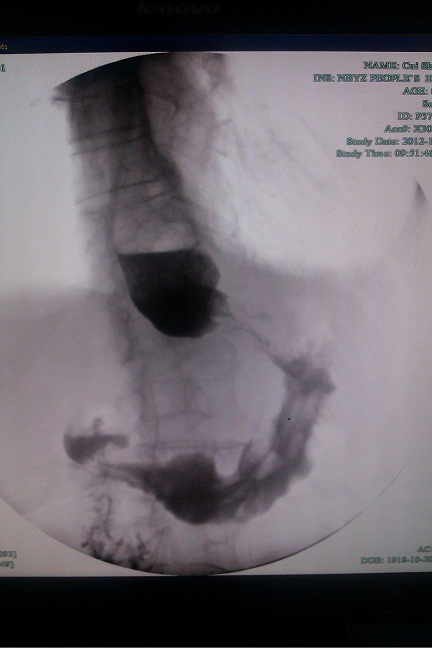

近期,我科就成功为一名94岁高龄男性近端胃癌患者成功放置了金属支架。该患者发现胃癌1年,近几个月开始出现进食后呕吐,但患者食欲很好,精神状态尚可,我们对该患者进行了评估,其有放置金属支架的指征,遂安排金属支架置入术。手术顺利,术后患者无明显腹痛等不适,进食后未再出现呕吐情况。虽然对于疾病本身,我们已无能为力,但该姑息治疗能解决患者不能进食的痛苦,一定程度上,延长了患者的生存时间。